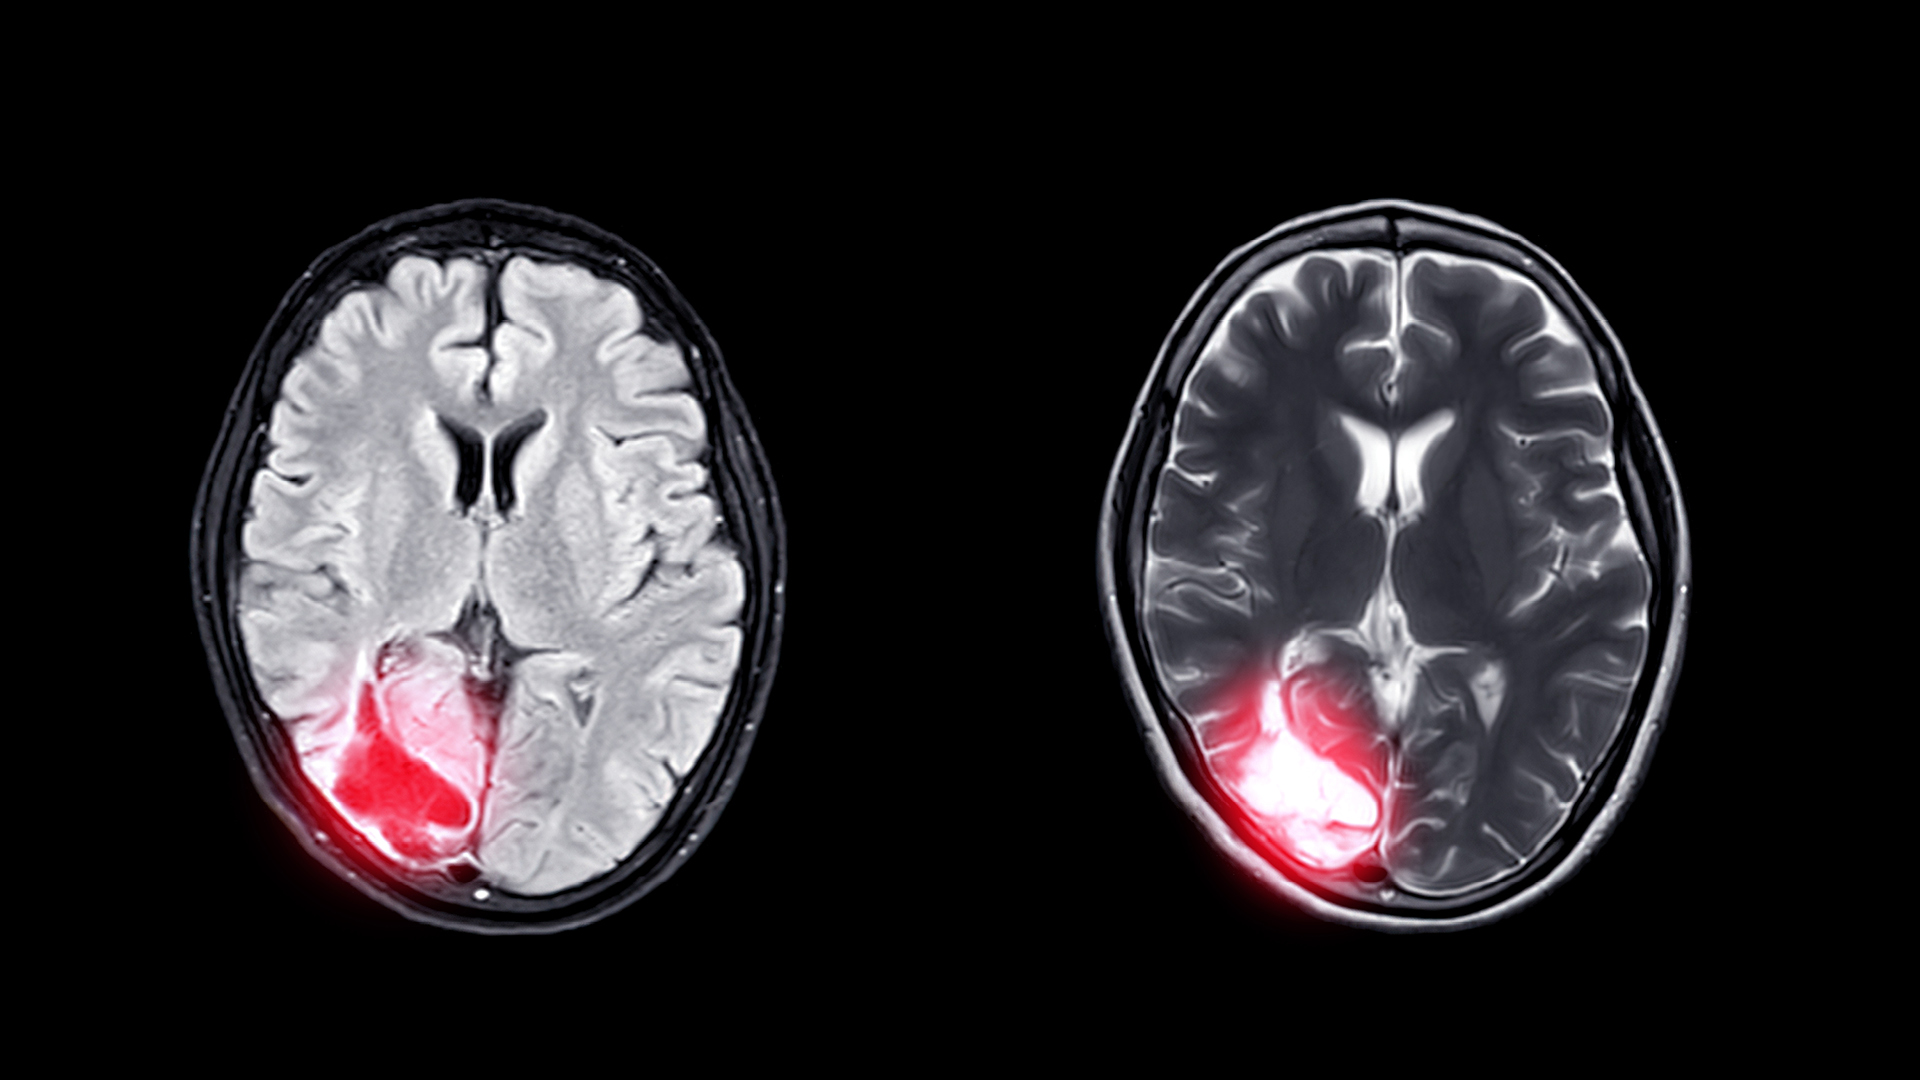

A degenerative disease, CTE causes the death of nerve cells in the brain. The early stages are commonly marked by mental health and behavioural issues, such as depression, anxiety and aggressive tendencies.

As the condition worsens, it increasingly impacts thinking and memory, with symptoms including speech difficulties and problems with movement and balance.

“Currently, CTE can only be diagnosed by examination of the brain at autopsy,”

explains Dr Michael Buckland, head of the department of neuropathology at Royal Prince Alfred Hospital in Sydney. “In fact, the current definition of CTE is based on the finding of an abnormally folded protein called tau in specific regions of the brain.”

Chronic traumatic encephalopathy (CTE) is a degenerative brain disease with some similarities to Alzheimer’s disease or frontotemporal dementia. The only known risk factor for developing CTE is exposure to repetitive head impacts (RHI), both concussions and sub concussive impacts.

In the past, CTE was thought to occur only in ex-boxers; however, we now understand that CTE occurs in a wide range of sportspeople exposed to RHI, as well as people who are exposed to RHI due to their work (military veterans, for example) or illness (people with very bad epileptic seizures).

There are many ways that CTE can manifest in life. In earlier or younger cases, people may have symptoms such as anxiety, depression, aggression and impaired impulse control. In later cases, in older people, the symptoms may mimic Alzheimer’s disease, with difficulties in thinking and short-term memory.